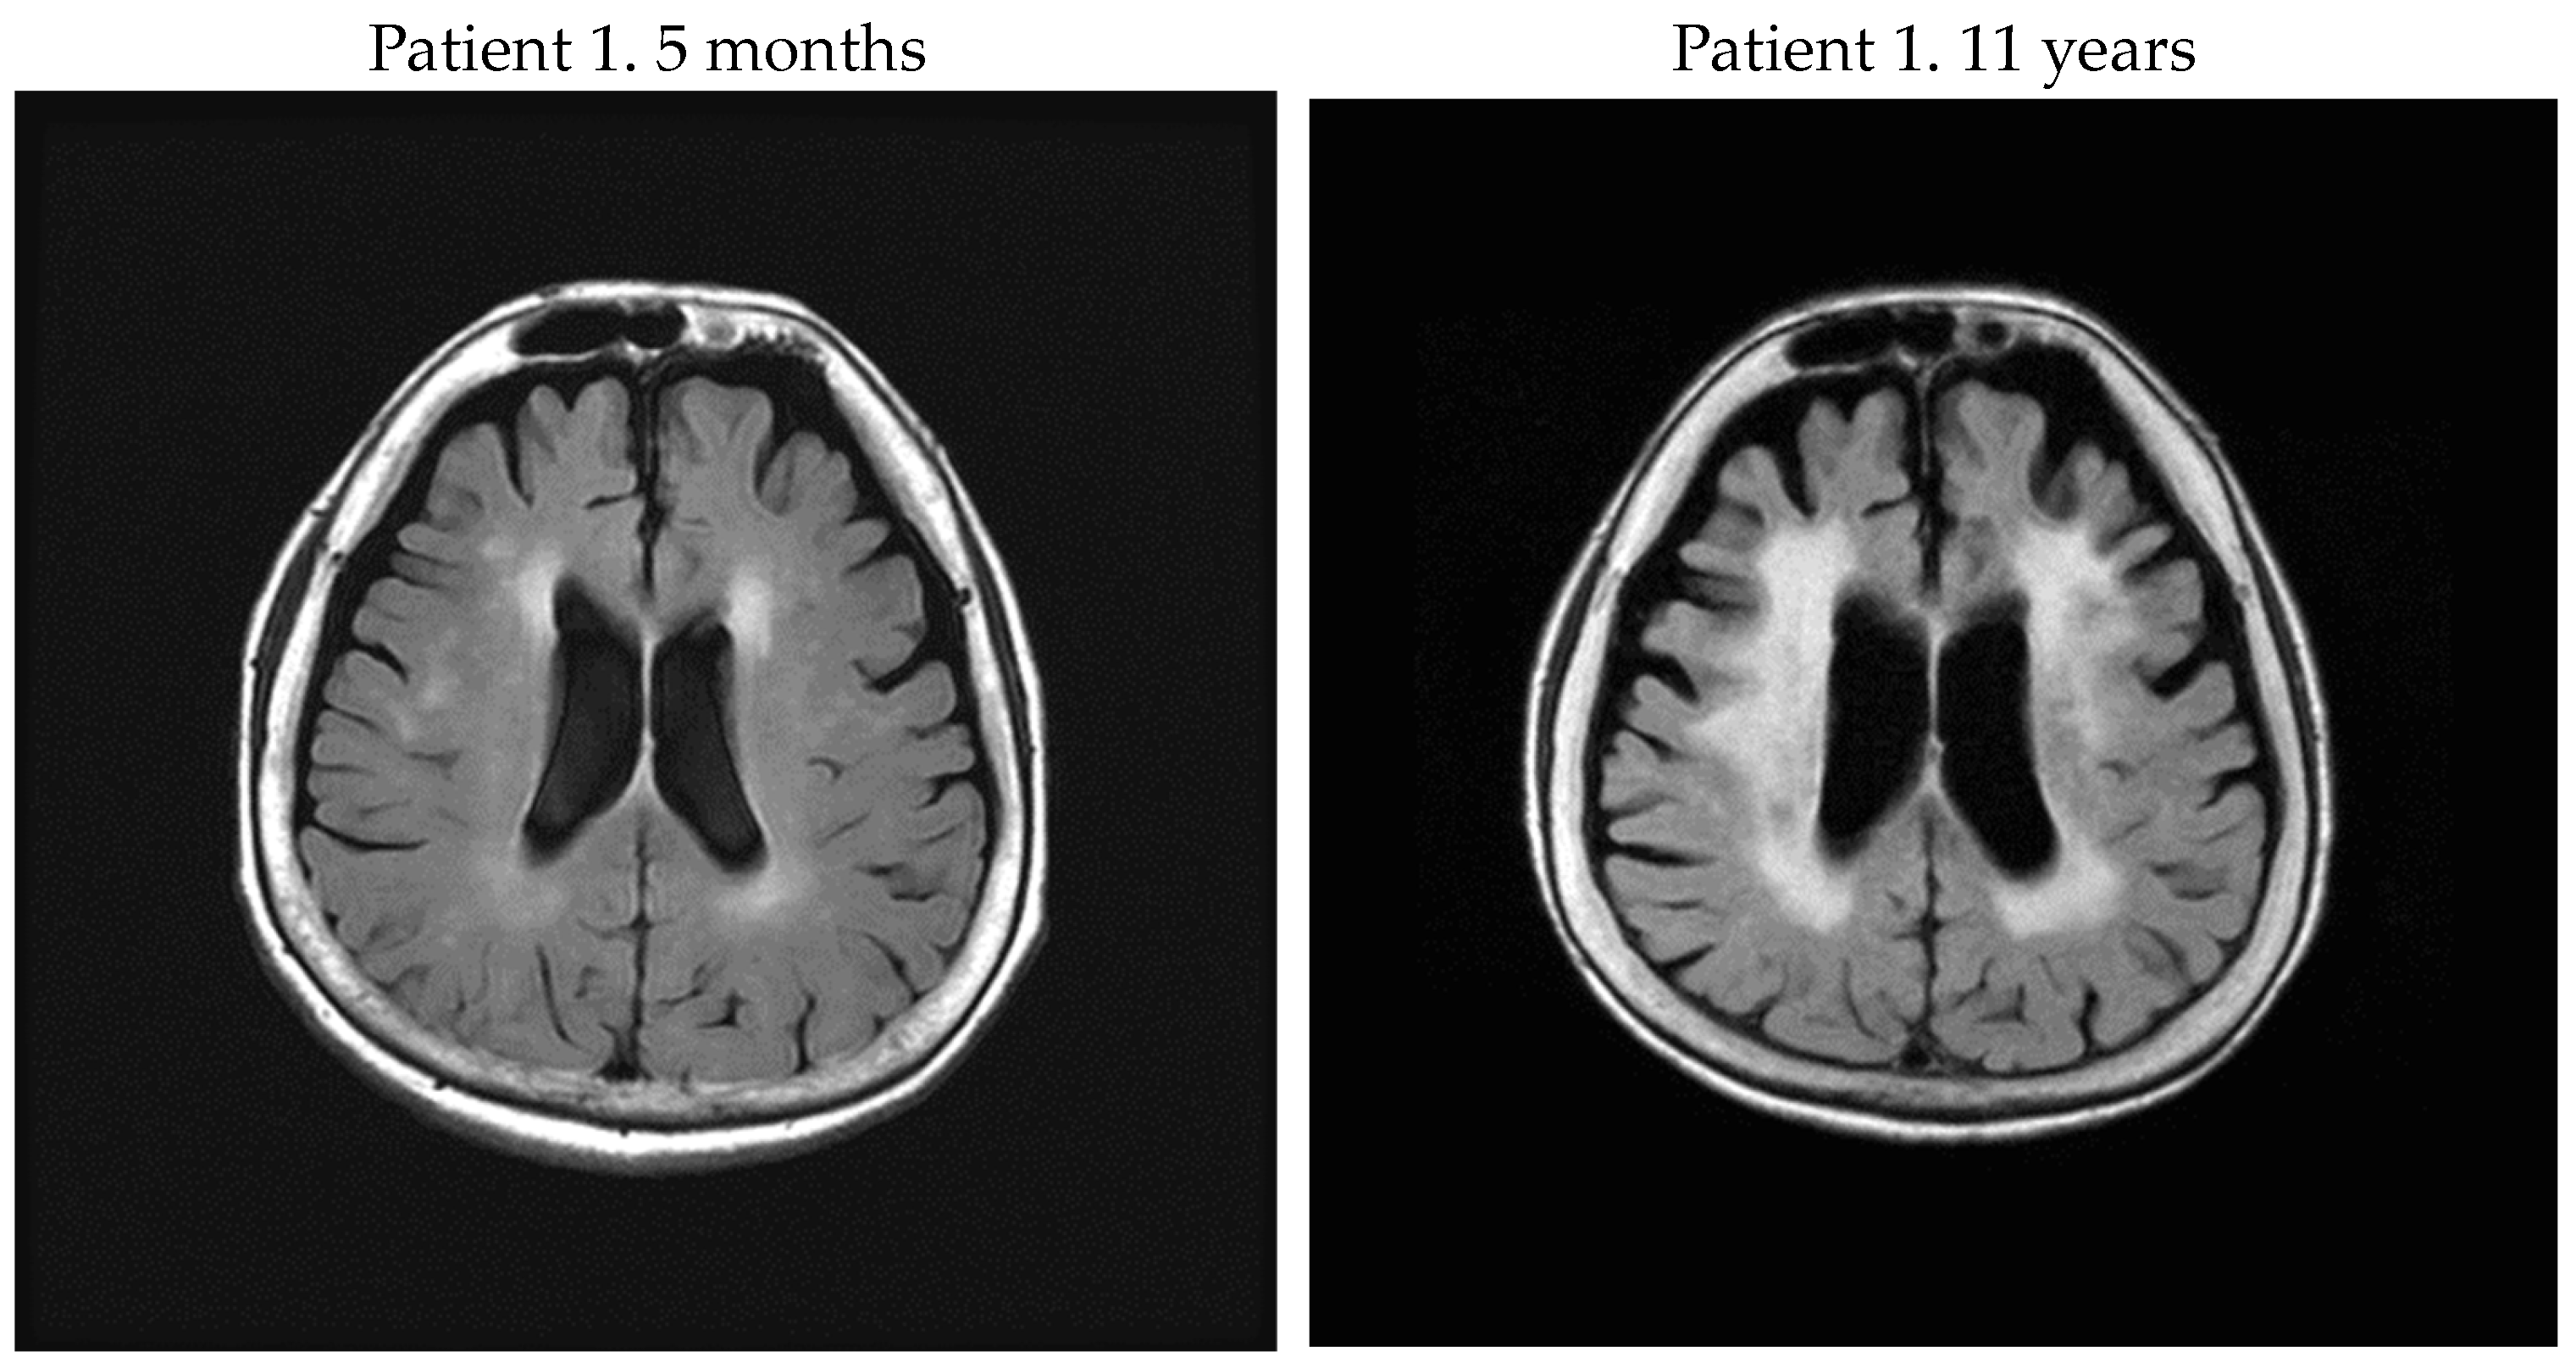

In this study, we evaluated brain WM lesions in patients with HAM/TSP. A final Fazekas scale 3 was more frequent in rapid progressors; conversely, among the group including slow and very slow progressors, only one had Fazekas scale 3. When the slow progressor who scored Fazekas scale 3 visited our department for the first time, it was already 33 years after onset, and her symptoms were severe with OMDS 13. Her cervical and thoracic spine MRI showed severe spinal cord atrophy, especially at the thoracic level. Of the five rapid progressors, three patients eventually presented with Fazekas scale 3 (Figure 1), and they had higher titers of CSF biomarkers (anti-HTLV-1 Ab titer, neopterin, CXCL10) than the other two patients. Regarding PVL in PBMC, there was a patient (patient 2) whose PVL was low among the rapid progressors with Fazekas scale 3. Furthermore, there were no correlations using Pearson’s correlation coefficient between Fazekas scale of PVH, DWMH, and PVL in PBMC at the last point in all patients.

Figure 1.

Of the 5 rapid progressors, 3 patients eventually presented with Fazekas scale 3, and they had higher CSF biomarkers (anti-HTLV-1 Ab titer, neopterin, and CXCL10) than the other 2 patients.